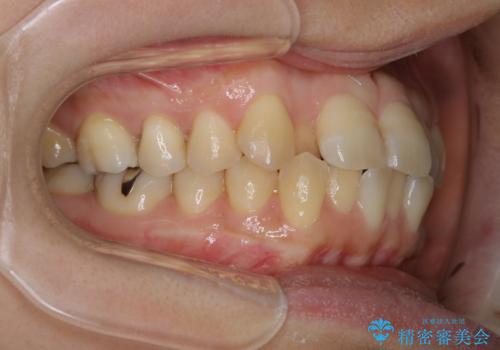

- 右上の2番目の歯が内側に入っているのと、下の前歯のがたつきが気になるとご相談にいらした方です。

上下左右の歯を後ろに動かして歯を並べるスペースを確保し、内側に入っていた歯を綺麗に並べ、前歯の中心もお顔の中心に合うようにしました。

矯正用アンカースクリューを埋入し、上下左右の歯を後ろに動かすことで歯を並べるスペースを作りました。

内側に入っている前歯が外に出てくる際、一時的に噛みづらくなることがあります。

元々内側に倒れていた右下の奥歯は、ゴムかけを追加で行っていただくことによりしっかり起こすことが出来ました。